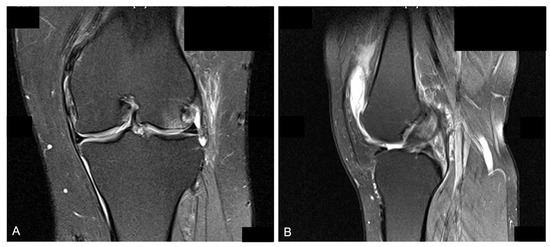

2.1. Preoperative Assessment

2.2. Surgical Procedure